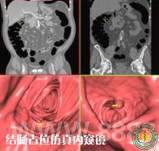

5.5 CT结肠仿真内窥镜检查

CT结肠检查的临床优势: 临床不能完成内窥镜检查的病人;可同时评估肠腔外腹部及盆腔器官的情况;可检查结肠皱襞后方的盲区;良好的病人舒适度与耐受性;软件自动探测可疑息肉样病变,提高诊断效率与信心。软件自动测量病变距离肛门距离,帮助制定手术治疗方案。